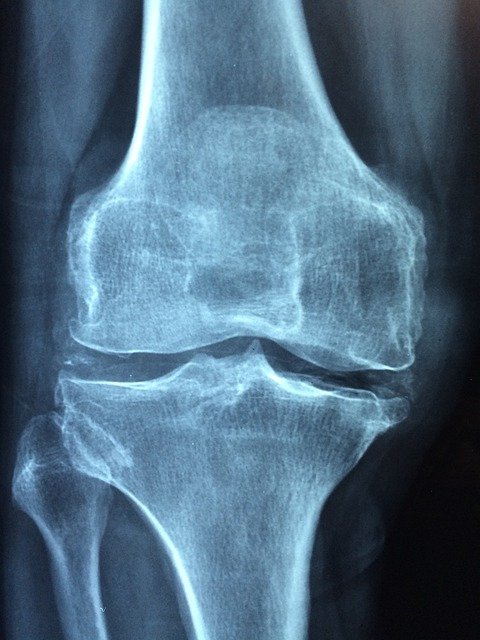

퇴행성 무릎 관절염은 연골이 닳은 정도와 관절의 퇴행 정도에 따라 1기 ~ 4기로 구분되며 X-ray로 확인 가능합니다.

x-ray로 확인 가능한 관절염 병기 (1기~4기)

- 1기 : 연골의 마모가 시작되어 가벼운 통증이 간헐적으로 나타나는 시기

- 2기 : 연골의 마모가 50% 미만으로 뼈에 골극이 조금씩 형성되지만 관절의 간격은 어느 정도 유지되는 시기

- 3기 : 연골이 반이상 닳아 있으며 골극이 커지고 관절의 간격이 좁아지는 시기

- 4기 : 연골이 다 닿아서 뼈와 뼈가 붙어있고 심한 골극이 자라고 o다리 형태로 다리 모양 변형

골극 : 뼈가시라는 의미로 뼈 위에 자라는 뼈를 말합니다. 잔뼈가 솟아난 모양으로 형성됩니다.

무릎 인공관절수술은 4기에 수술해야 합니다. 4기에는 잘 때는 물론, 가만히 있어도 지속적이고 극심한 통증이 있고 무릎을 굽히거나 펴는 활동이 어려워집니다.